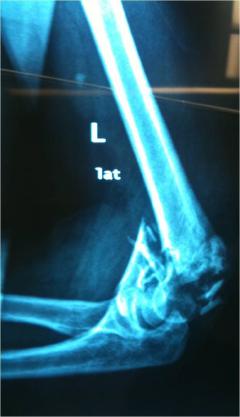

Περίπτωση 2ου ασθενούς

Προεγχειρητική